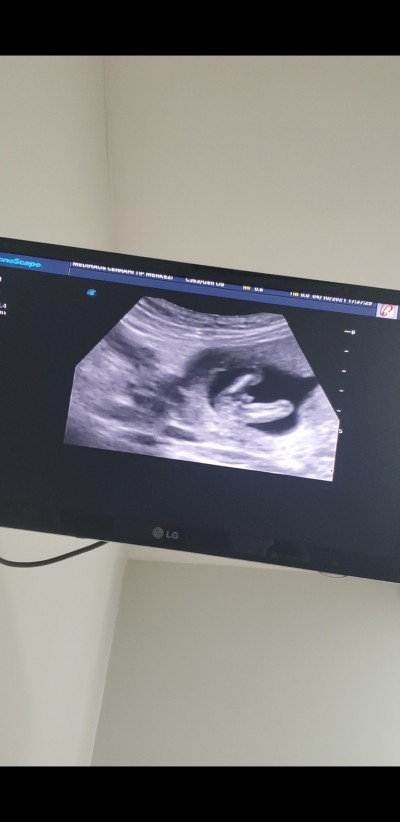

Kızlar tahminlerinizi alabilir myiim ? Doktor kesin değil ama erkek olabilir dedi haftaya birdaha bakacağız

Gebelik haftası 15